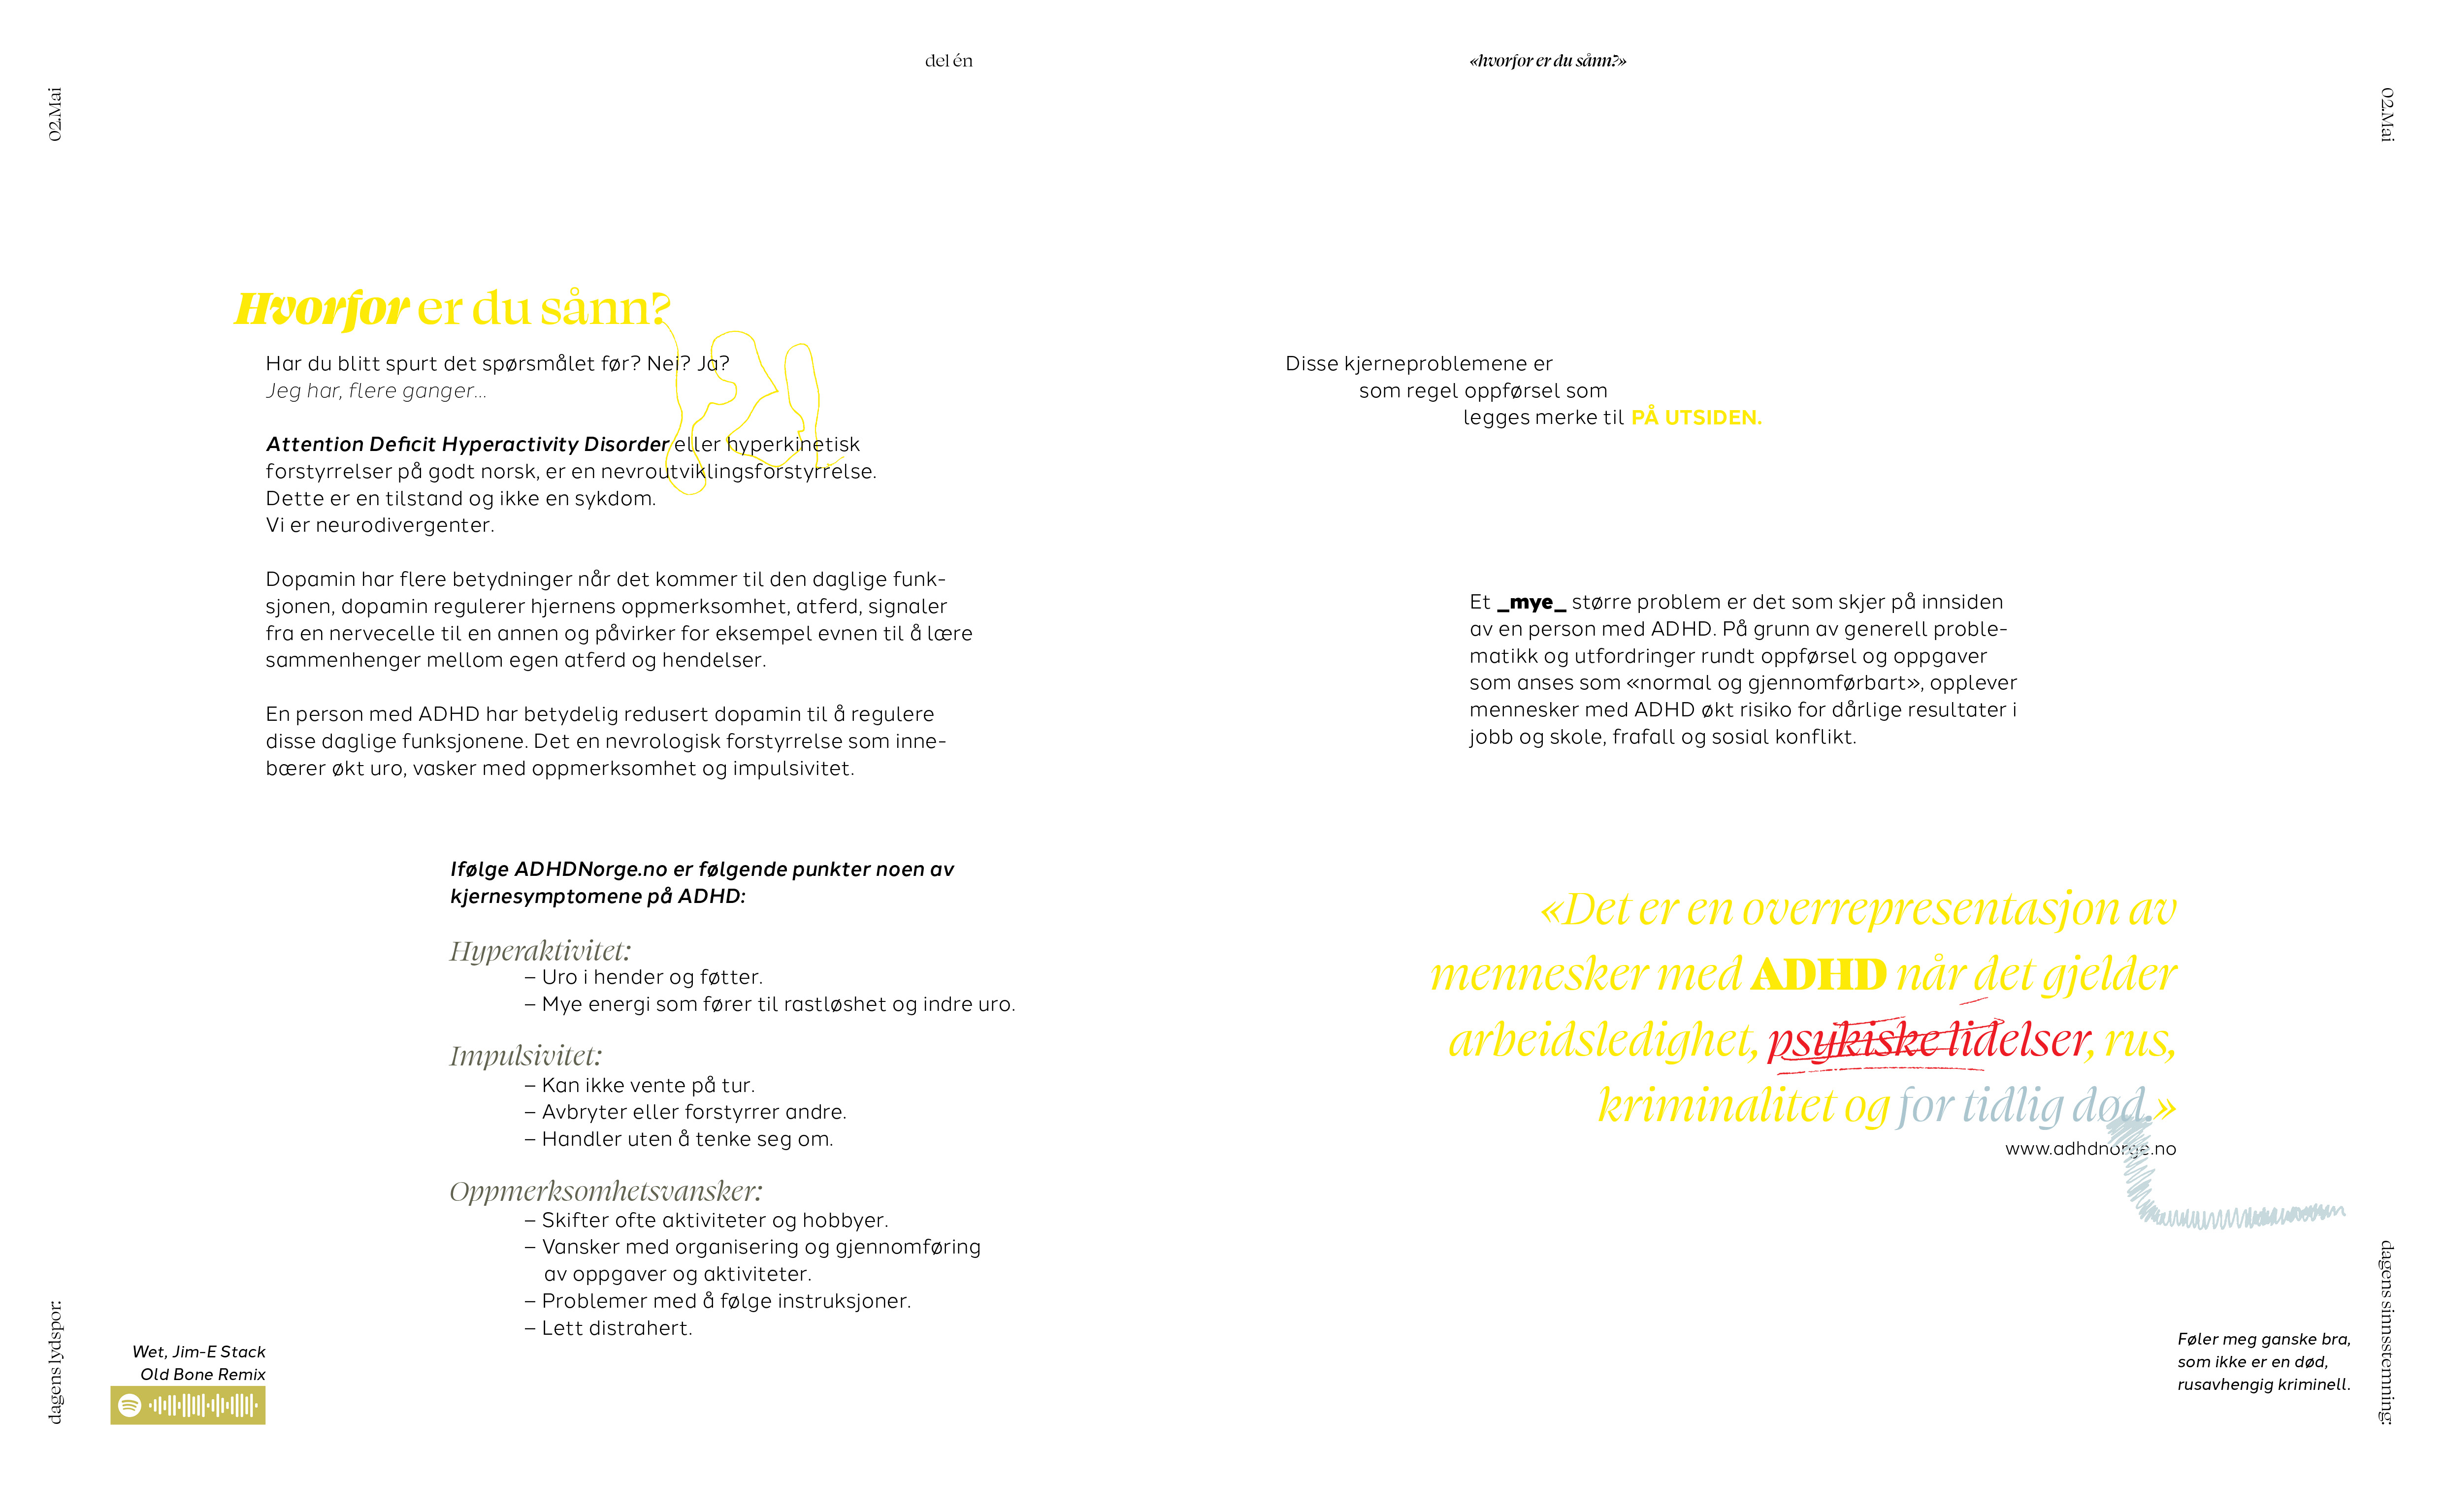

Hvordan er hverdagen til en kreativ ADHD-voksen og hva er egentlig

ADHD? Denne boken er laget for å være et visuelt hjelpemiddel for

mennesker som er nevrodivergenter. Både for å skape tilhørighet og

forståelse, men også vise til visualiseringer for å formidle følelser som

kan være vanskelige og kommunisere.

Ønsket er at det skal være mulig å få en tilnærmet opplevelse hvordan

psykisk helse kan oppleves, slik at også pårørende kan få et innblikk i

hvordan en hverdag kan oppleves, når den til tider bare er kaotisk.

Denne boken er skapt av en ADHD-voksen

for andre ADHD-voksne.